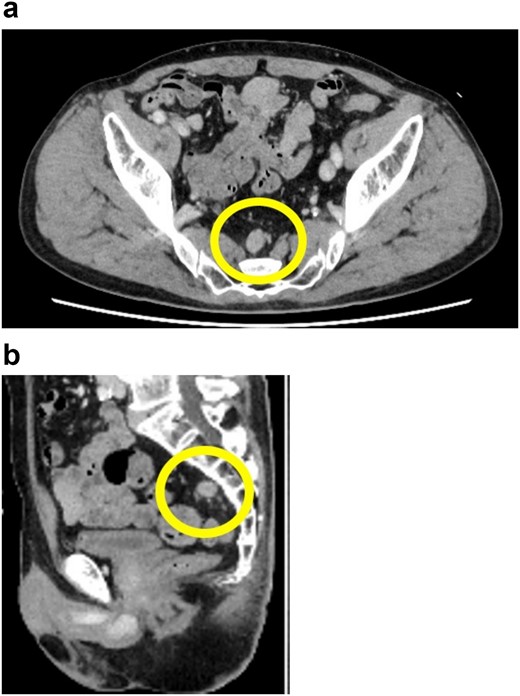

A 72-year-old man diagnosed with NSCLC was referred for possible surgical treatment of a solitary nodule detected in the mesorectum. His medical history included hypertension and endoscopic resection of colonic polyps, with no prior thromboembolism. He had received combined medical treatment for NSCLC (cT4N0M0, stage IIIA) (Fig. 1), including four courses of cisplatin and docetaxel chemotherapy with a 60 Gy/30 fractions radiation dose, followed by 1 year of consolidation therapy with durvalumab (640 mg/body). The patient tolerated the treatment well, achieving a complete response 13 months before presentation (Fig. 2). However, the mesorectal nodule was incidentally discovered during surveillance CT after NSCLC treatment completion. It was round, 15 mm in diameter, showed contrast enhancement, and was near the mesorectal vessels (Fig. 3a and b). An FDG PET/CT scan revealed a solitary mesorectal nodule with an SUVmax of 10.3 (Fig. 4). Consequently, the radiologist suggested differential diagnoses of malignant lymphoma and metastatic lymph nodes from the urinary or lower gastrointestinal tract, as NSCLC typically does not metastasize to mesorectal lymph nodes. No other abnormal FDG uptake was observed. Laboratory tests showed normal levels for tumor markers, including carcinoembryonic antigen, sialyl Lewis X (SLX), squamous cell carcinoma antigen, neuron-specific enolase, cytokeratin fragment (CYFRA), progastrin-releasing peptide, and blood coagulability was within the normal range. Total colonoscopy revealed no neoplastic lesions, and urinary cytology showed nonmalignant urothelial cells. Noninvasive diagnostic approaches, including endoscopic or CT-guided biopsy, were extensively discussed but deemed difficult because of anatomical restrictions, risk of dissemination, and procedure-related complications (such as bleeding or perforation). Because of the potential malignancy and need for en-bloc resection, we opted for surgical resection using a standardized laparoscopically assisted mesorectal excision technique. During rectal dissection, the nodule was not visible through the posterior and lateral sides because it was completely embedded in the mesorectum. Therefore, a Pfannenstiel incision was made in the lower abdomen to exteriorize the rectum after the division of the proximal colon. The nodule was confirmed by direct palpation, marked with a stitch, and subsequently removed after intracorporeal transection of the distal rectum. We inspected the resected specimen and confirmed that the nodule was incorporated (Fig. 5a and b). A colorectal anastomosis was then performed using a double-stapling technique with a circular stapler. The postoperative course was uneventful, except for a slight elevation of the d-dimer level (up to 3.26 μg/ml) on postoperative Day 7, which normalized spontaneously without intensive anticoagulation therapy. The patient was discharged on postoperative Day 10. Pathological examination revealed that the 7-mm white nodule was an intravenous organized thrombus in the mesorectum surrounded by granulation tissue, with no malignancy observed (Fig. 6a and b). Postoperatively, the patient did not require additional chemotherapy or anticoagulation therapy. During the 16-month follow-up, no radiological evidence of NSCLC recurrence and thromboembolism was detected (Fig. 7).

Preoperative pelvic computed tomography (CT) image. The circle indicates the nodule located in the mesorectum. (a) Horizontal view. (b) Sagittal view.